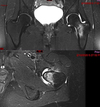

Arthroscopic image of a knee shows the posterior cruciate ligament bundle origins. The anterolateral bundle (ALB) and the posteromedial bundle (PMB) are observed at their origin on the lateral side of the medial femoral condyle (MFC), or the medial intercondylar notch.

A

• primary restraint to posterior tibial translation, greatest instability at 90 of flexion.

• AL tight in flexion, strongest/most important for stability at 90 “PAL” PCL

• PM tight in extension.